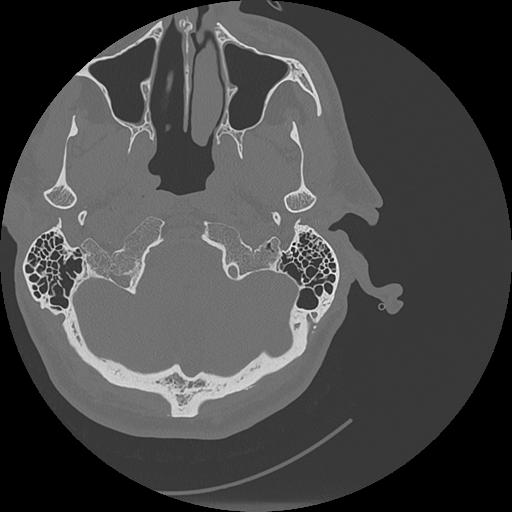

7 HUESO,,Vol,0.5,HUESO,,